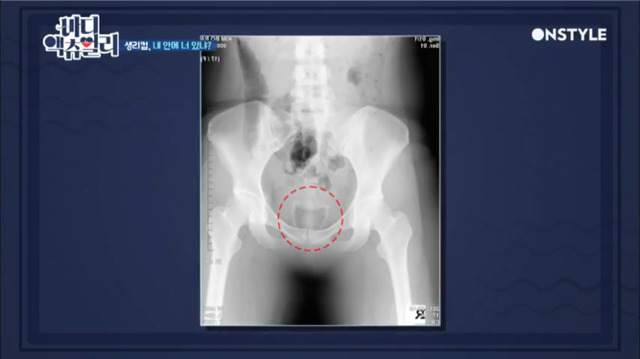

생리컵은 실리콘 형태로 되어있는 여성 용품으로 질 내부에 삽입해 사용하는 제품이다.

생리컵은 꼬리만 바깥쪽으로 나오게 된 후 질에 넣어 사용하는 제품이다. 따라서 삽입할 때 구겨서 넣더라도 질 안에서 자연스럽게 퍼져 단단히 고정된다.

생리컵은 입구 부분을 누르면서 잡아당겨야 빠지도록 설계된 구조로, 오히려 생리대에 비해 눕거나 엎드려도 샐 가능성이 매우 적다.